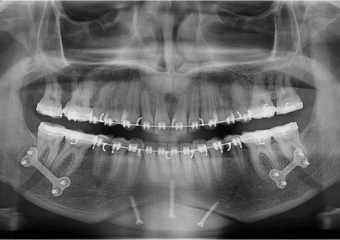

Raio X inicial